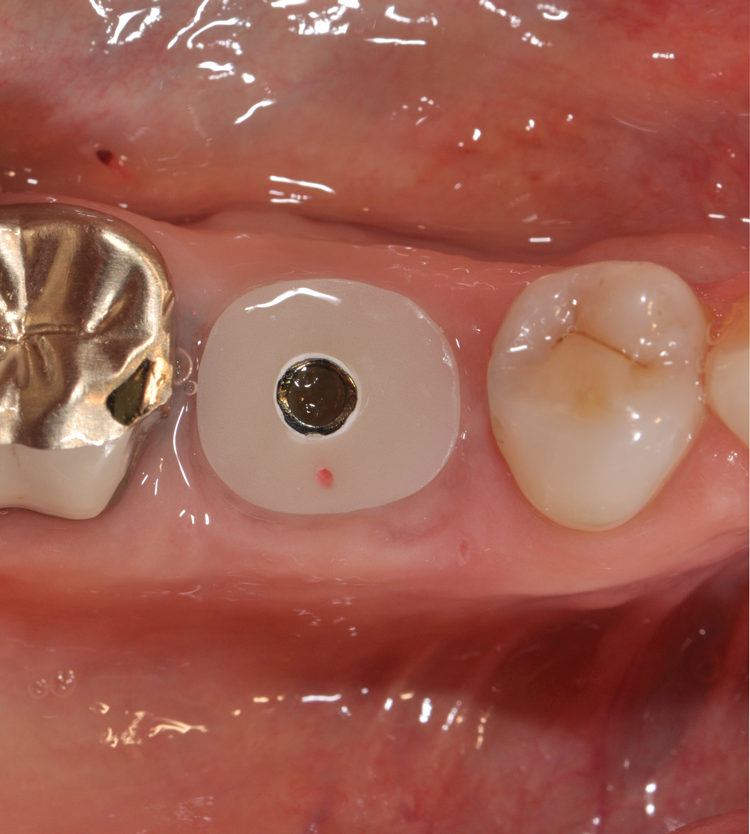

(8.) Restoratively centered guided osteotomy and implant insertion.

Figure 8